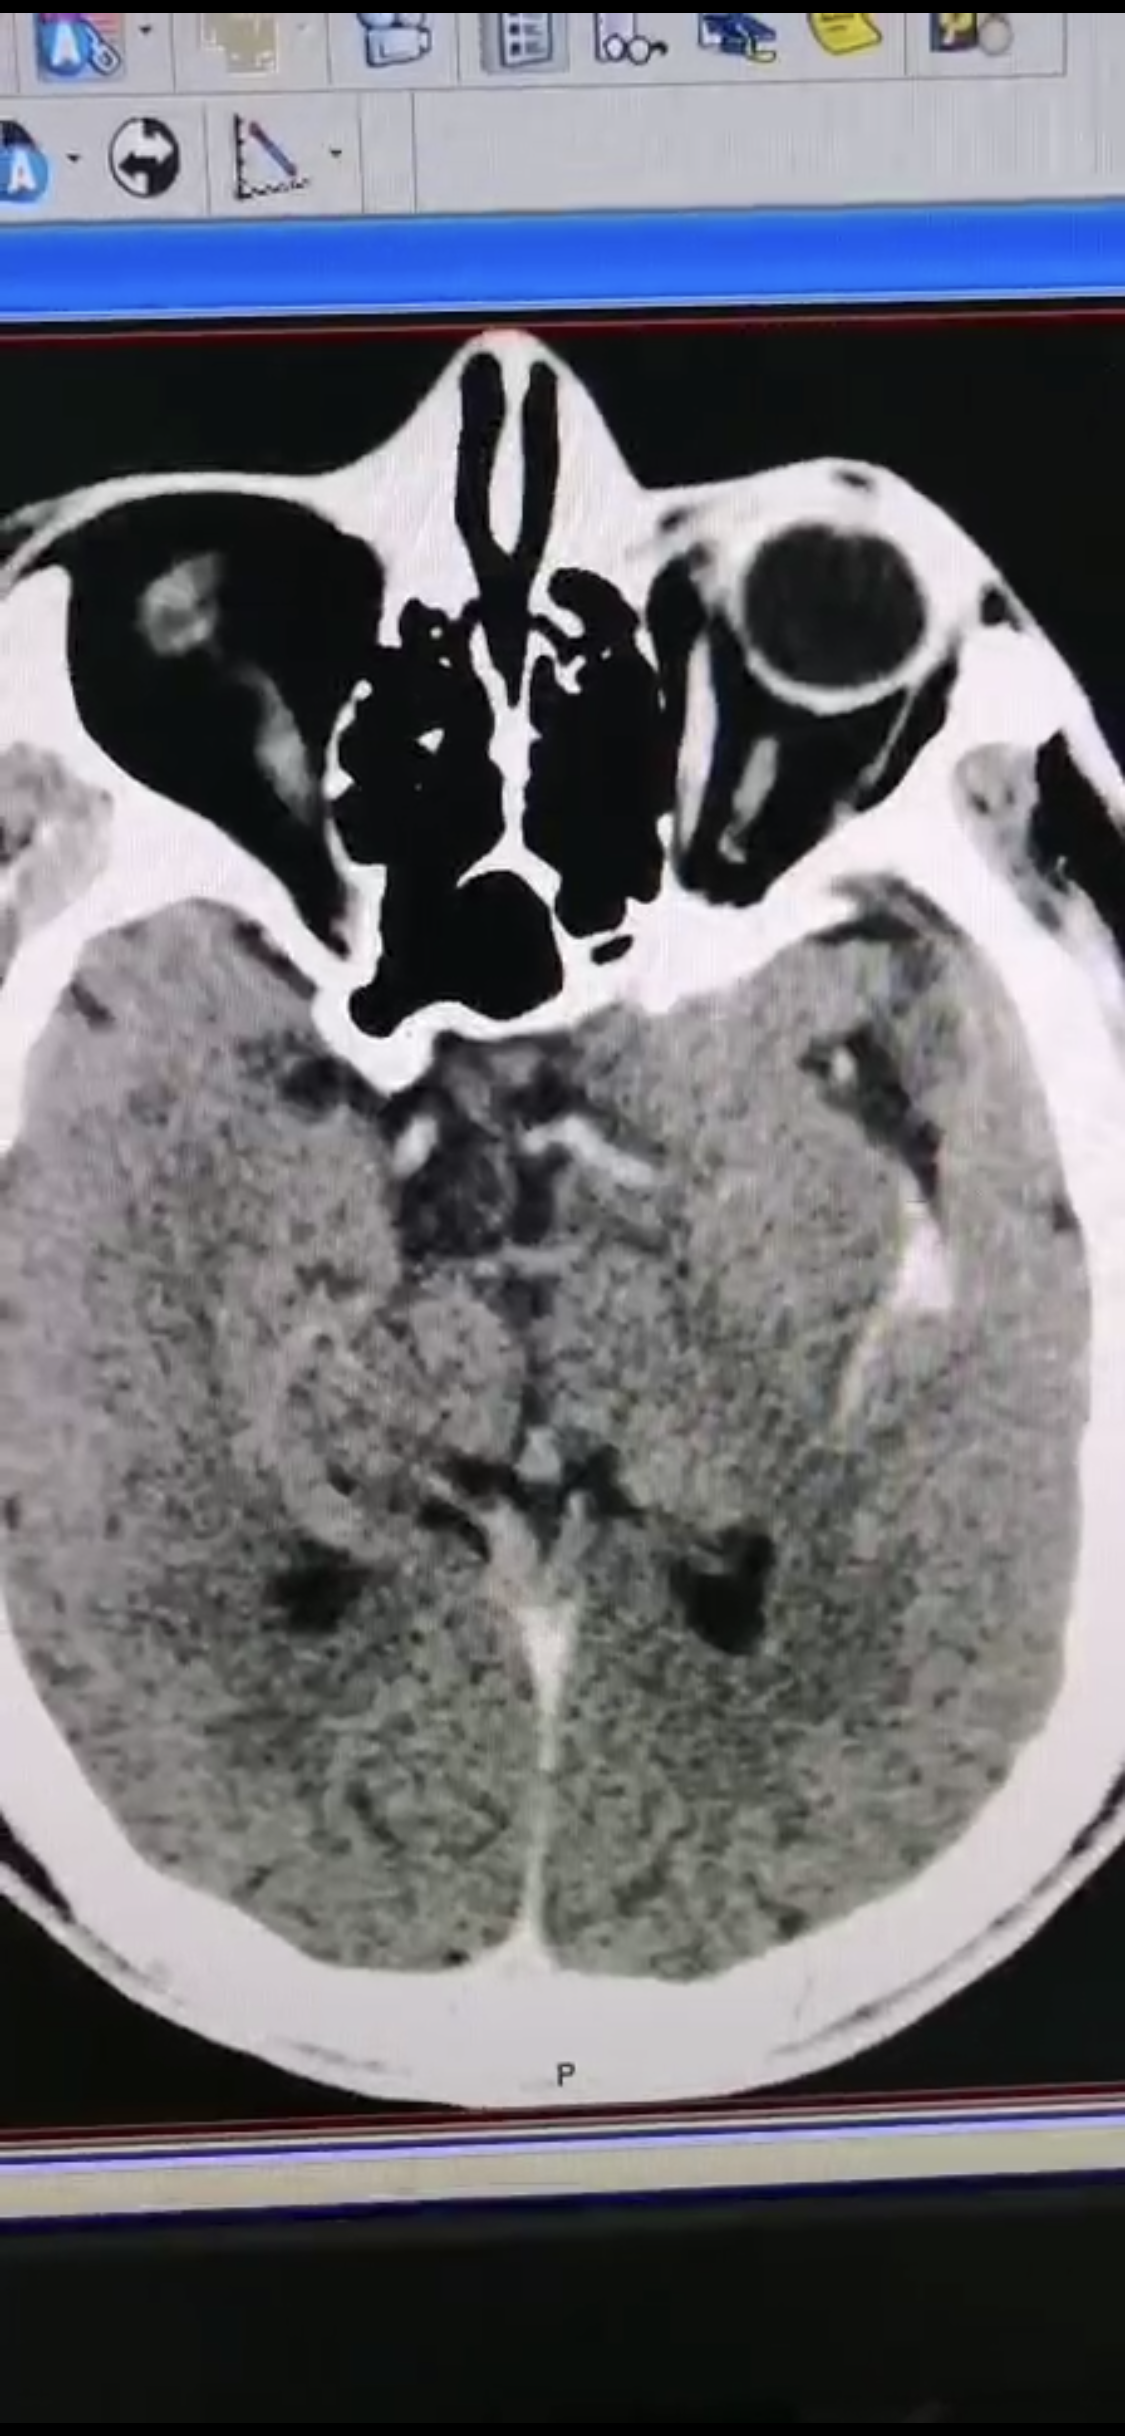

急诊二。zde,f53y。

意识模糊进行性加重8h,基底动脉闭塞,reco取栓再通,貌似动脉硬化,实际血管光滑。造影➕取栓8min。今日团队配合紧密,不到三小时全麻造影取栓带苏醒完成两台取栓。团队棒棒的!南阳市中心医院神经内科脑血管病介入团队